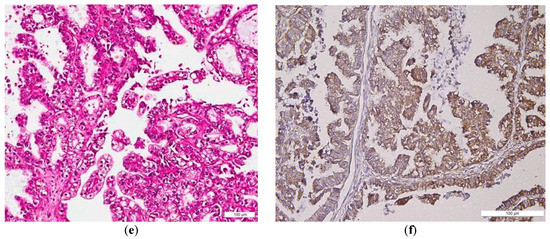

2.1. BMI-1 Expression—Qualitative Assessment